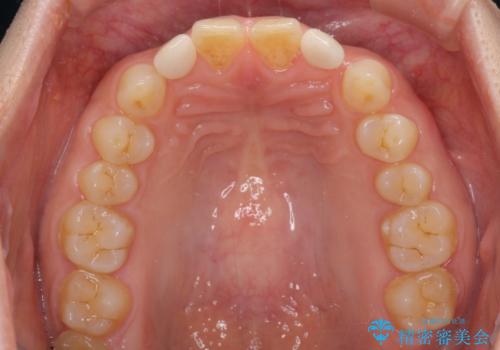

前歯の隙間や、周りの歯と色合いの違いなどはあまり気にしていらっしゃらなかったため、矮小歯の2歯を自然な大きさに仕上げました。

とても自然な歯が装着されたとのことで、患者様には大変満足していただきました。